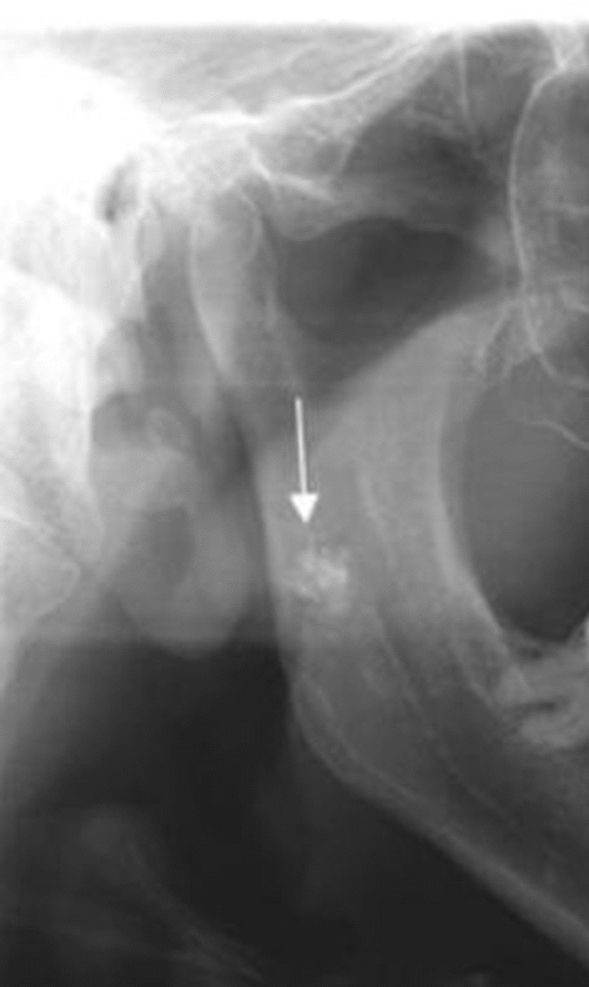

Fig. 7.

a, b Well defined, bilateral nodular radiopacities were seen at the level of the lower margin of the third and the fourth cervical vertebra (C3 & C4). Based on the radiographic location and appearance of the lesion on the radiograph, a provisional diagnosis of the coronary artery calcification was made